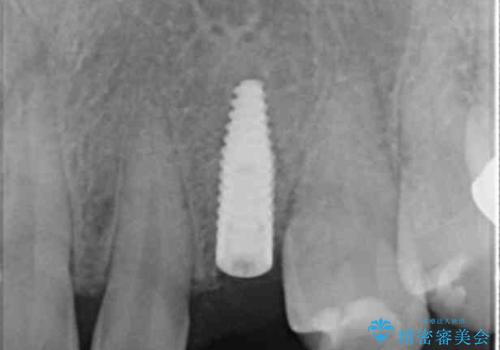

骨造成を伴う 前歯部インプラント治療

適切なインプラント埋入を行い、不足している骨量を補うため骨の造成を併用したインプラント治療を計画します。

前歯のインプラント治療は骨量・歯肉の厚み・インプラントの方向をしっかりと計画することで、審美的で長持ちを期待できるような仕上がりとなります。